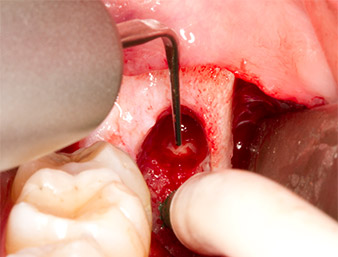

Piezomed B5

Fig. 5: L'osso nella regione dell'alveolo è sollevato con uno strumento piezochirurgico a forma di scalpello (Piezomed B5). Tale osso è utilizzato come materiale autologo di rinforzo dopo la rimozione del residuo di radice (vedere Fig. 13 e 14).

Per ottenere materiale autogeno per il successivo trattamento della ferita, sono stati estratti frammenti di osso sano nella zona del residuo di radice con uno strumento piezochirurgico (Piezomed B5) (Fig. 5).

Il tessuto autogeno è stato rimosso con la sezione a forma di raschietto della parte funzionante dello strumento e conservato un una soluzione salina fisiologica per uso successivo (vedere Fig. 13).